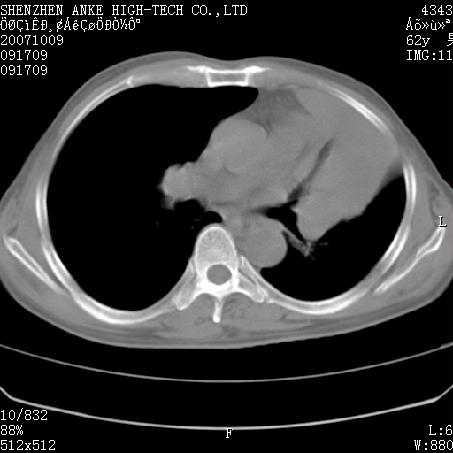

患者:男,62岁,咳嗽、胸痛、咯血约2月

左侧中央型肺癌伴上叶肺不张\\阻塞性肺炎.

考虑左侧中央型肺癌伴上叶肺不张\\阻塞性肺炎,我觉得穿刺病理明确最好。应该很容易穿得。

左侧中央型肺癌伴上叶肺不张、阻塞性肺炎、纵隔淋巴结转移。支持!

左侧中央型肺癌伴上叶肺不张及阻塞性肺炎,纵隔内淋巴结转移